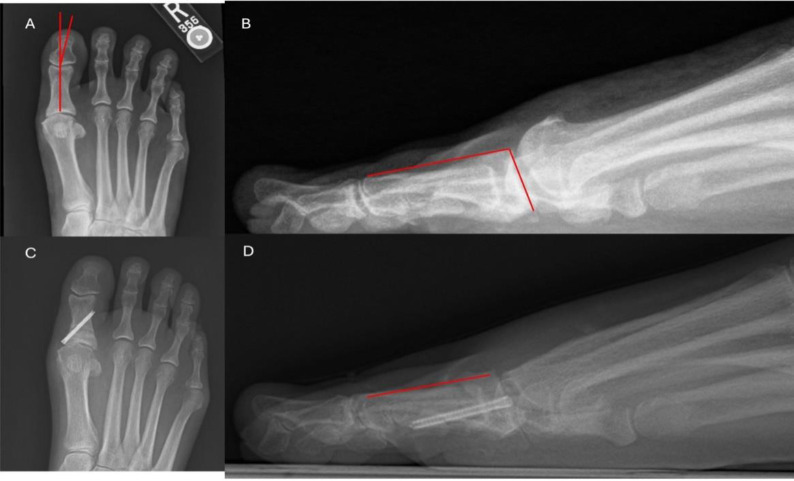

Objectives: Current literature on surgical techniques has evaluated minimally invasive surgery (MIS) cheilectomy and its efficacy in comparison to the open technique. However, no study to date has evaluated MIS-Moberg in relation to open and MIS cheilectomy. This study assessed radiological outcomes and early healing and complications of patients who underwent open, MIS, and MIS-Moberg cheilectomies.

Methods: We conducted a retrospective cohort review of 134 patients who underwent first metatarsophalangeal (MTP) cheilectomy at an academic medical center between 2015 and 2024. Success of cheilectomy was determined radiographically. Postoperative complications were identified through medical record review.

Results: 73 open and 61 MIS cheilectomies were performed on 134 patients with a primary diagnosis of hallux rigidus. The pre-operative versus post-operative differences in dorsal cortical length (3.7±1.4) and sagittal articular P1 angle (7.3±4.8) were found to be statistically significant (P<0.05) for the MIS-Moberg group. Ten patients in the open cheilectomy were found to have dorsiflexion and plantarflexion stiffness compared to zero patients in the MIS and MIS-Moberg groups (P<0.01).

Conclusion: We showed a significantly greater rate of plantar- and dorsiflexion stiffness in open surgeries compared to MIS and MIS-Moberg. No other differences in healing rates or radiologic outcomes were observed. Based on preliminary results, the MIS-Moberg can successfully alter the radiographic alignment of the great toe and does not increase complications as compared to open or MIS cheilectomy alone.